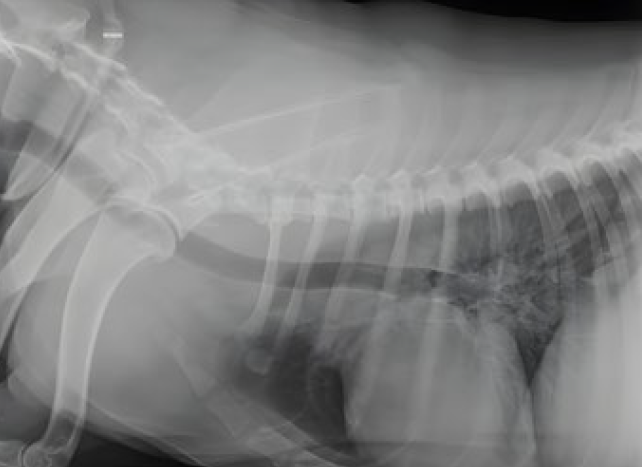

Los tumores de mama caninos (TMC), son los tumores más frecuentes en perras, siendo más frecuentes en edades más avanzadas, aumentando significativamente a partir de 8 años de manera lineal y siendo raros en perras menores de 5 años. (Foto 1)